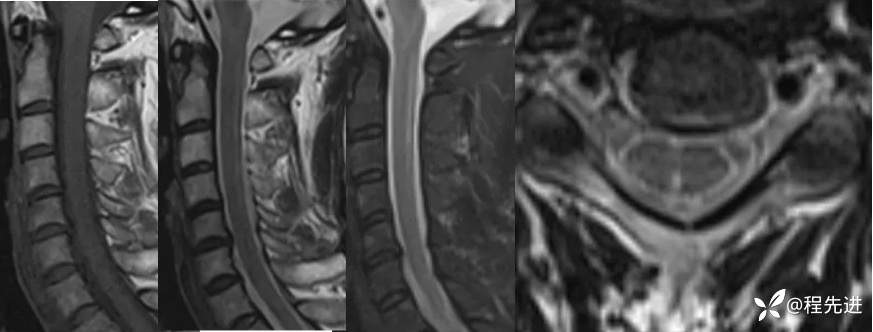

颈椎MRI平扫: